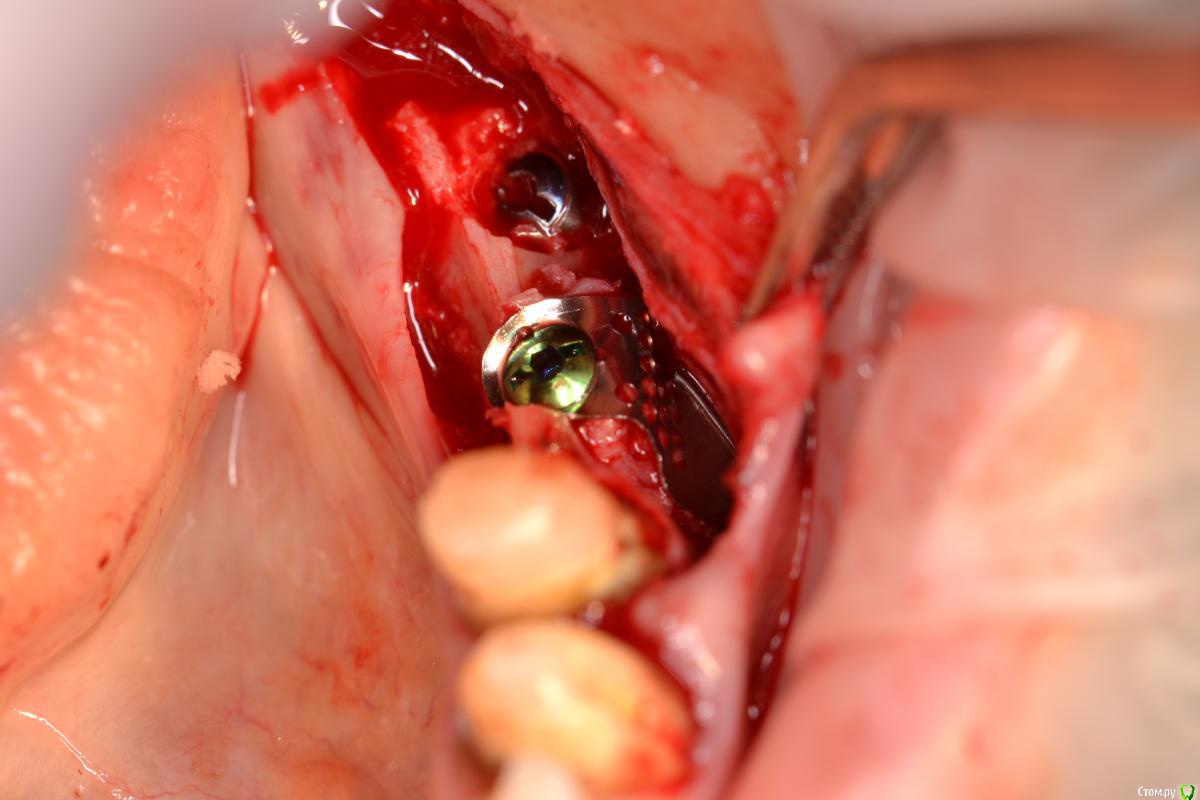

Makalester Опубликовано 27 ноября, 2016 Поделиться Опубликовано 27 ноября, 2016 Друзья, подскажите как лучше поступить в данном случае? Ламина, цитопласт, коллагеновая мембрана? Смущает тонкий монокортикальный гребень, выживет ли под ним что нибудь. Ссылка на комментарий

Makalester Опубликовано 28 ноября, 2016 Автор Поделиться Опубликовано 28 ноября, 2016 а какими методиками владеете? Здесь цитопласт или "кюри" Кюри не делал. Жесткие каркасы каркасы 50/50 , то нормально все, то оголится. Последнее время все больше сосидж 50ауто- 20 алло- 30 ксено, но тут смущает что питания мало((. Вот думаю если ламину или остеогвард, они резорбируются дольше чем биогайд и эволюшн? Ссылка на комментарий

Makalester Опубликовано 28 ноября, 2016 Автор Поделиться Опубликовано 28 ноября, 2016 я бы вообще не заморачивался бы,имплант на 7ММ заглубить немного и если надо спейсером перекрываем слишком большая яма получится( Ссылка на комментарий